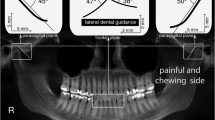

The cephalometric images were recorded using a digital CRANEX D Digital X-ray unit (73 kV, 10 mA, 17.6 s, CC-detector sensor; Soredex, Tuusula, Finland). The first author measured all images using the NemoCeph 2D software (Nemotec, Madrid, Spain). Hard tissue points were used as landmarks during cephalometric analysis, with the reference planes consisting of the Frankfort, mandibular, and cranial base planes (Table 1). Seven linear and fifteen angular parameters were used for sagittal skeletal analysis. All parameters are shown in Figs. 3 and 4.

Table 4 shows the correlations between cephalometry values and TMD signs. Limited mouth opening was significantly associated with a small angle formed by N–Pog to the Frankfort plane (P = .020), and large ANB angle (P = .035). TMJ crepitus significantly associated with large angles of: S–N–Pog (P = .039), ANB (P = .001), the angle formed by N–Pog to the Frankfort plane (P = .036), and the upper gonial angle (Ar–Go–N, P = .023).

TMJ tenderness was found statistically associated with a short effective mandibular length (Co–Gn, P = .014), a short anterior facial height (N–Me, P = .003), small angles between: mandibular plane and palatal plane (P = .009), mandibular plane and S–N (P = .048), and mandibular plane the Frankfort plane (P = .017). Participants with muscle tenderness had a large upper gonial angle (Ar–Go–N, P = .024) but small lower gonial angle (N–Go–Me, P = .025). Lower anterior facial ratio (Ans–Me/N–Me) was significantly associated with a limited mouth opening (P = .042), TMJ crepitus (P = .027), and TMJ tenderness (P = .002).